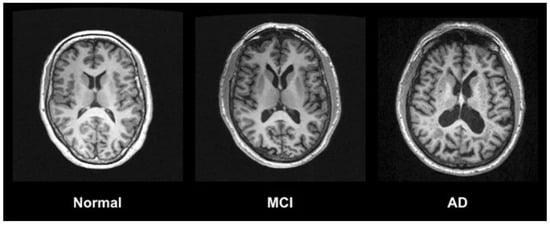

- Chandra, A.; Dervenoulas, G.; Politis, M. Magnetic resonance imaging in Alzheimer’s disease and mild cognitive impairment. J. Neurol. 2018, 266, 1293–1302. [Google Scholar] [CrossRef]

| MRI | Magnetic Resonance Imaging |